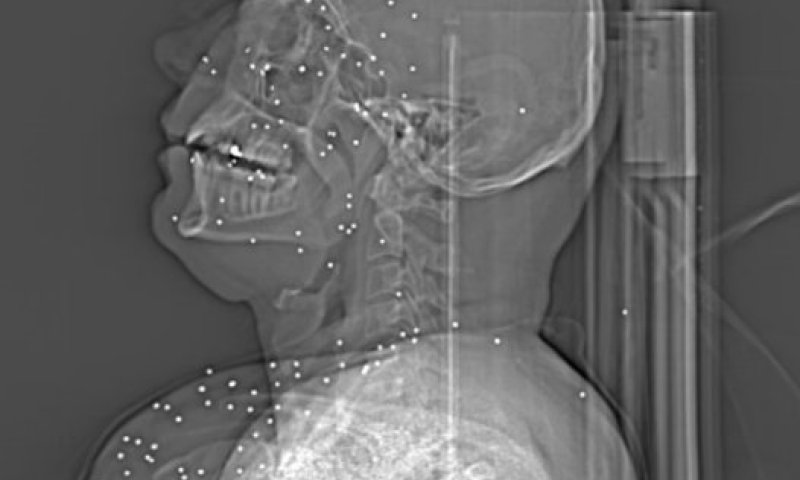

בסדרה של תצלומים ודימויים שנחשפה, שבוצעו על ידי צוותים רפואיים באיראן בזמן ההתקוממות נגד שלטון האייתולות חושפת שימוש שיטתי בירי חי כנגד אותם מפגינים, במטרה להרוג, לפצוע להטיל מומ ונכות. קובץ של עשרה תצלומי ראש שבוצעו על ידי רופאים בטהראן מראה שימוש קבוע ברובי ציד (שוטגאן) כנגד מפגינים, כולל שימוש בכדורי רסס, כדורים המכילים עשרות כדוריות עופרת המתפצלים ומבצעים פגיעה רחבה.

על פי אותם תצלומים, נעשה שימוש תדיר בכלי זה כנגד מפגינים, בירי בכינון ישיר אל ראשים, פנים ואיברים חיוניים. צוותים רפואיים עצמאיים שבחנו את הצילומים העריכו כי מרבית הפצועים ששרדו את הטבח יסבלו מנזקים כבדים לאורך חייהם, נזקים כמו עיוורן, חירשות, נזק מוחי, נכות ופגיעות מנטליות שונות.